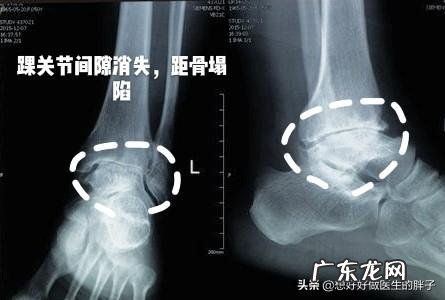

这种情况最基本的也要到医院进行x线检查,而如果x线没有发现明显骨头损伤的话,需要进行核磁检查明确关节内是否有软骨损伤或者是韧带的撕裂 。如果明确有韧带或者是软骨的损伤,要咨询专业的医生是否进行专业的固定,而自己进行单纯的包扎,可能并不能达到非常好的zhi疗效果 。无论如何适当的加压包扎、冰敷、抬高、休息都是zhi疗踝关节损伤的基本原则 。●观察是否有关节的畸形 。这种情况,如果出现了,往往就证明骨头有了明显的折断,一定要减少活动,如果周边有小木板或者是晾衣架,要给予踝关节,周边进行简单的固定,之后打120,或者是由他人搀扶下,避免损伤关节的负重,去医院进行检查,进行相应的zhi疗 。